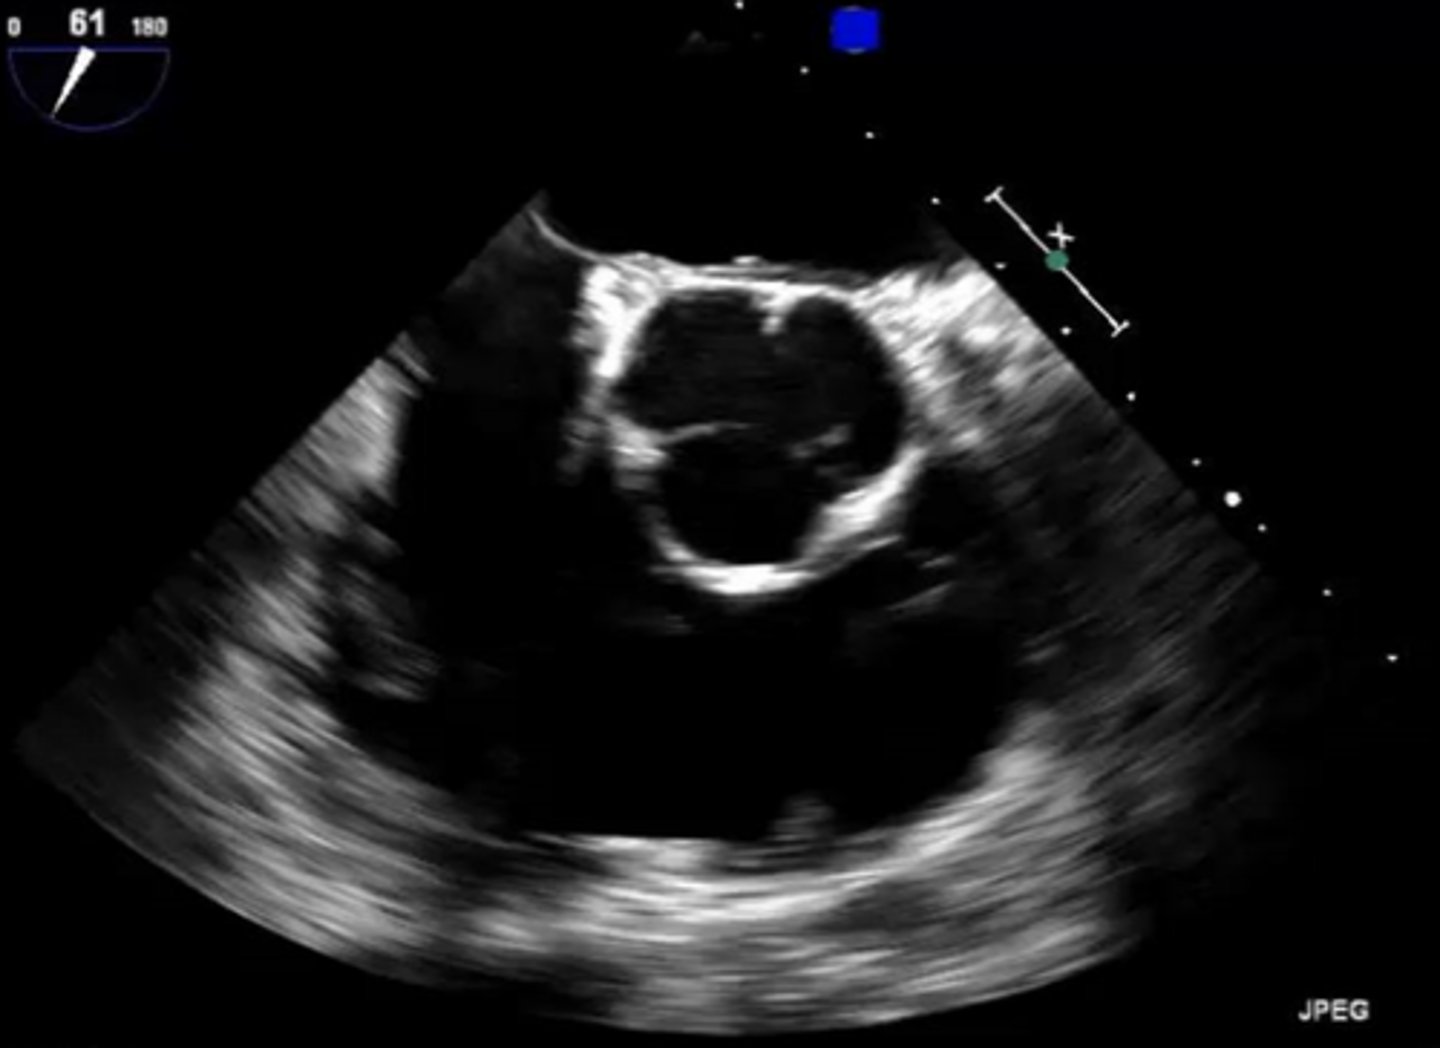

AoV 3CA (left cusp)

non-coronary cusp

AoV 3CA (right cusp)

right coronary cusp

MV 3CA (left leaflet)

posterior mitral valve leaflet

MV 3CA (right leaflet)

anterior mitral valve leaflet